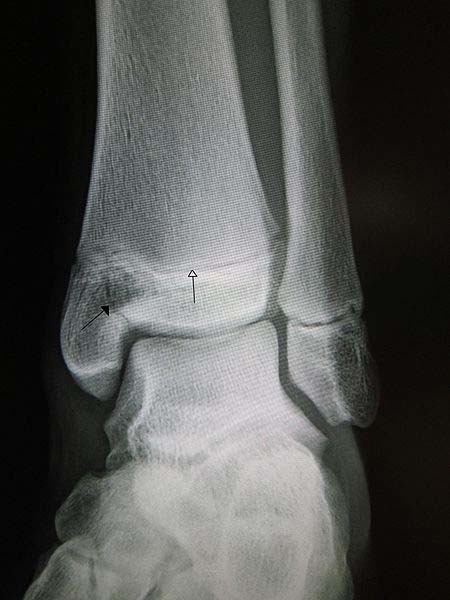

The ankle joint and the associated ligaments can be visualised as a ring in the coronal plane.

Identify and describe the borders of this ring

In light of the ankle ring, discuss what is meant by stable and unstable ankle fractures

What is a Pott’s Fracture-Dislocation?

A Pott’s fracture is a term used to describe a bimalleolar (medial & lateral malleoli) or trimalleolar (medial & lateral malleoli, distal tibia) fracture which occurs due to the force eversion of the foot